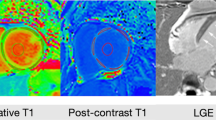

LGE presence and extent were similarly distributed between the groups (Table 2). There were no differences between native T1 times measured at the septum or the average from all segments. There were also no differences between the two groups in native and post-contrast blood T1 times. However, post-contrast T1 times, both at the septum and the average were significantly lower in patients with AB. Similarly, ECV in nearly all myocardial segments, including the septum as well as the global ECV were significantly larger in patients with AB (Table 2, Supplementary Table 2, Fig. 1). Except for the native blood T1 times, which were similar between DCM patients and age- and sex-matched controls, all other T1 parametric measures differed between the two groups (Supplementary Table 1).

Assessment of interstitial fibrosis

T1 mapping was performed using (Siemens Skyra VE11 with MyoMaps) a Modified Look Locker Inversion (MOLLI) Recovery sequence before and 15 min after gadolinium-based contrast agent injection. The following typical MOLLI sequence tfi2Dl parameters were used: breath-hold TR/TE of 281/1.1 ms, slice thickness of 8 mm, FOV from 320 × 260 mm2, matrix of 144 × 256 pixels, flip angle of 35°. Native and post-contrast T1-values were determined by drawing regions of interest (ROI) in every segment of the basal, mid-ventricular slice as well as in the centre of LV cavity for measuring T1 blood pools. ROIs were drawn in mid-wall region of the myocardial segments and were copied between native and post-contrast T1 maps (Fig. 4A,B). Segments with artifacts were excluded. The global native, post-contrast T1 times as was well as ECV were calculated as a mean of all segments. Septal ECVs were calculated as the mean of mid-myocardial 8 and 9 segment (assessment blinded to the clinical data, P.B). ECV was calculated according to the established formula:

Native and post-contrast contours in the mid-myocardial area. The left ventricular cavity is shown (orange in native T1-mapping and dark-blue in post-contrast T1-mapping) to enable derivation of blood and myocardial T1 values. Standardized ROIs are placed in the septum to measure native (A) and post-contrast T1-times (B).